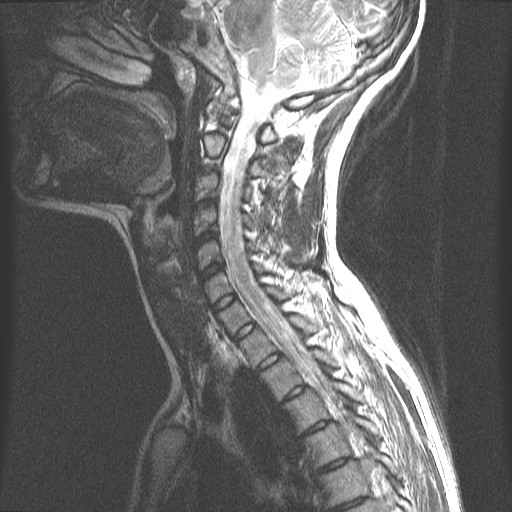

CWZ